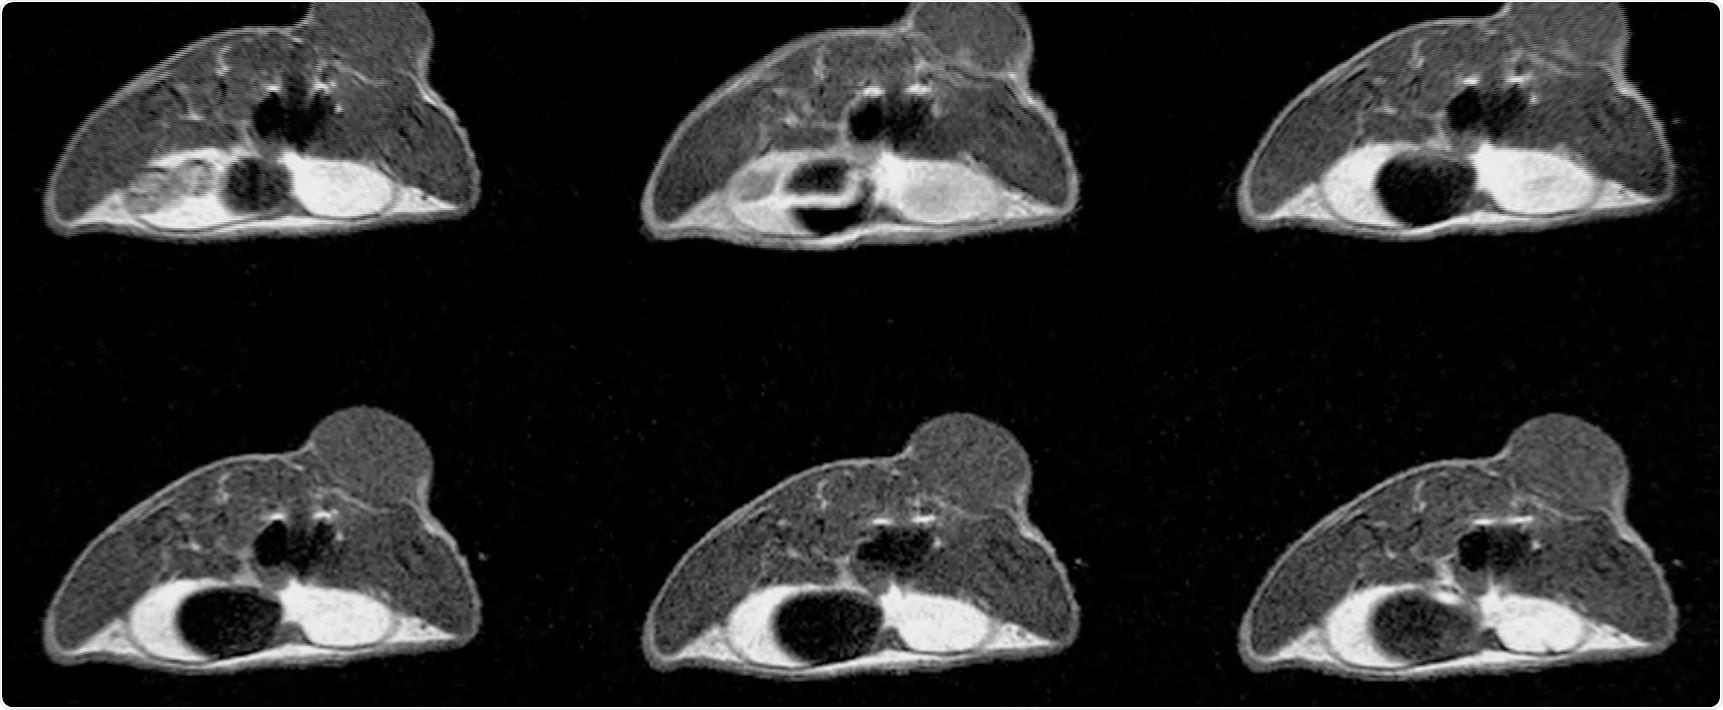

On the other hand, 1Tesla ICON system can provide high-contrast imaging with contrast agents and it is very easy to use. It is also important that the contrast is similar to that of clinical MRI scanners.

For example, with our manganese with calcium phosphate micelle, we used 7Tesla system for MR angiography and MR spectroscopy and ICON system for T1-weighted MRI. I believe that it is the optimal combination for the application.